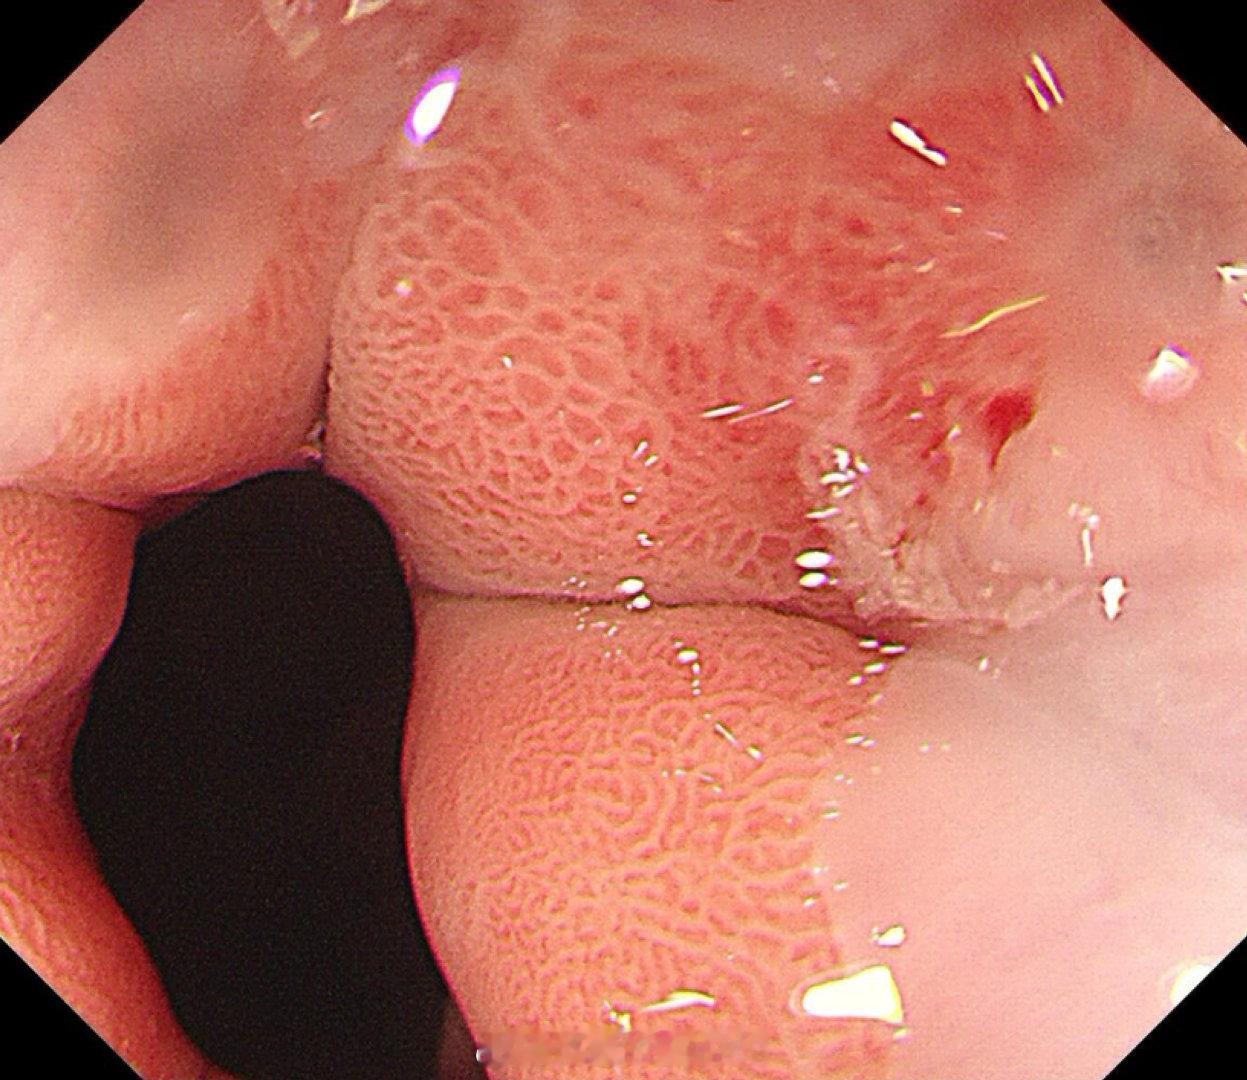

这是个兄弟医院做的内镜发现有贲门病灶,老人体型腹型肥胖很典型,返流持续那么多年导致的Barrett食管癌风险肯定是最高的,她女婿找我精查会诊了一次,我看着病灶虽小,但是有点僵硬,感觉已经到了黏膜下的barrett食管癌,但是他们都想尝试切除看看浸润深度,诊断性esd实施后黏膜下550微米,一般来说这地方超过500微米已经是sm2,淋巴结转移风险急剧加大了,后面就要纠结要不要追加外科手术,但是这个手术做了生活质量会相当不好。所以这种癌的最好措施是预防,发现非常困难,往往一发现就是深了。腹型肥胖的人群减重以减少返流是很重要的。